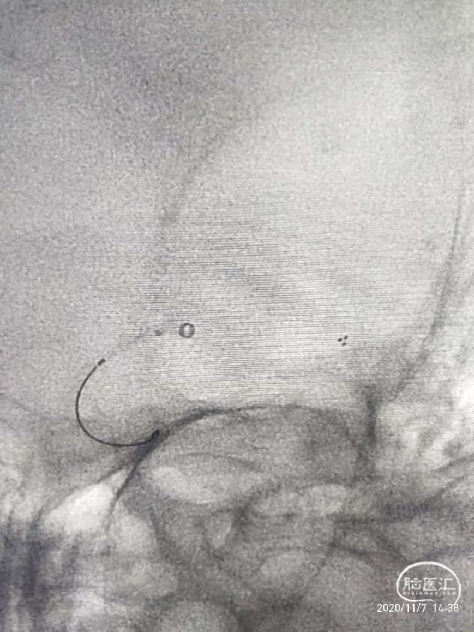

将6F Neuron Max长鞘置于左侧颈内动脉C2段,微导丝微导管引导下将ACE68抽吸导管置于左侧大脑中动脉M1段开口处,退出微导丝,置入4*20mm支架,支架远端位于M2段,释放支架等待5分钟。

支架释放5分钟后在持续负压抽吸下,采用抽吸导管抽吸结合支架取栓技术取出约4cm血栓1枚,术毕即刻造影左侧颈内动脉、大脑中动脉、大脑前动脉血流完全再通,mTICI评分3级。